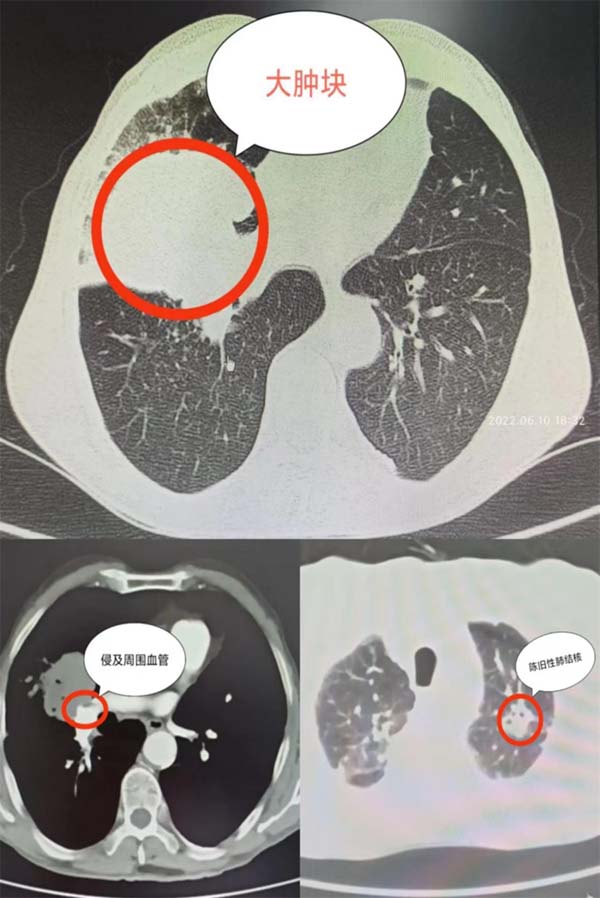

近 1个月,段大爷越发消瘦,咳嗽、活动后喘息症状日渐加重,遂到医院复查胸部CT提示肿瘤进展,肿块已达8.8cm*7.6cm。“肿瘤已侵及右肺门大血管,这个手术难度大、风险高、技术要求高,而且老爷子有陈旧性肺结核和慢性阻塞性肺病的病史,肺功能差,这也增加了手术的难度和风险……”段大爷一家人跑遍当地所有医院都是无功而返,一家人焦急万分。经多方打听,应急总医院胸外科主任陈静瑜教授不仅是“中国肺移植第一人”,而且在局部晚期肺癌手术方面经验丰富,于是段大爷的女儿带着父亲从山东老家来到北京就诊。

应急总医院胸外科杨龙海副主任看到患者的检查单时发现:肿瘤虽然大且已侵及肺门大血管,但远处无转移,有肺部肿瘤根治性手术的机会,如果手术成功,将大大改善患者的生存质量,延长患者的生命。陈静瑜教授查看患者的病例后表示:“我们的技术可以帮助到段大爷,虽然风险高但还是有希望的!”